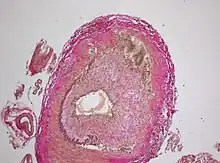

The gold standard for diagnosing temporal arteritis is biopsy, which involves removing a small part of the vessel under local anesthesia and examining it microscopically for giant cells infiltrating the tissue.[23] However, a negative result does not definitively rule out the diagnosis; since the blood vessels are involved in a patchy pattern, there may be unaffected areas on the vessel and the biopsy might have been taken from these parts. Unilateral biopsy of a 1.5–3 cm length is 85-90% sensitive (1 cm is the minimum).[24] Characterised as intimal hyperplasia and medial granulomatous inflammation with elastic lamina fragmentation with a CD 4+ predominant T cell infiltrate, currently biopsy is only considered confirmatory for the clinical diagnosis, or one of the diagnostic criteria.[11]

The pathological mechanism is the result of an inflammatory cascade that is triggered by an as of yet undetermined cause resulting in dendritic cells in the vessel wall recruiting T cells and macrophages to form granulomatous infiltrates.[19] These infiltrates erode the middle and inner layers of the arterial tunica media leading to conditions such as aneurysm and dissection.[19] Activation of T helper 17 (Th17) cells involved with interleukin (IL) 6, IL-17, IL-21 and IL-23 play a critical part; specifically, Th17 activation leads to further activation of Th17 through IL-6 in a continuous, cyclic fashion.[19] This pathway is suppressed with glucocorticoids,[20] and more recently it has been found that IL-6 inhibitors also play a suppressive role.[19]

Radiological examination of the temporal artery with ultrasound yields a halo sign. Contrast-enhanced brain MRI and CT are generally negative in this disorder. Recent studies have shown that 3T MRI using super high resolution imaging and contrast injection can non-invasively diagnose this disorder with high specificity and sensitivity.[25]